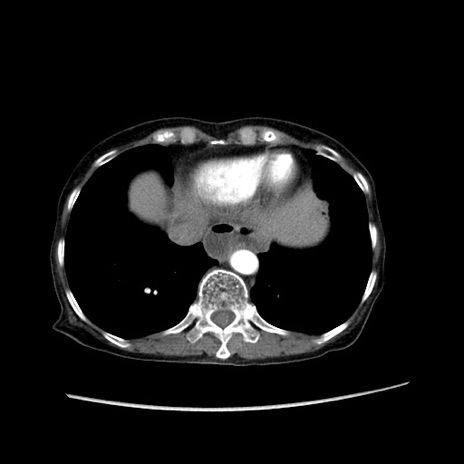

症例25(横断像)

【症例】80歳代女性

【主訴】胸のつかえ感

【現病歴】約9時間前に食後から胸のつかえた感じあり、嘔吐あり、来院。

【既往歴】胃癌(全摘)、胆摘、虫垂炎

【身体所見】心窩部に圧痛あり、反跳痛なし。

【データ】WBC 5700、CRP 0.05